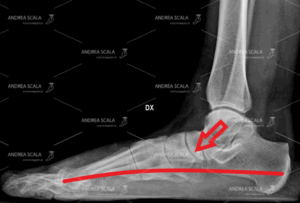

La RXgrafia pre-operatoria del paziente di settanta anni. Si vede il crollo dell’arco del piede. L’astragalo sprofonda verso il suolo perché i legamenti mediali sono sempre stati lassi. Il piede è sato trascurato è sempre stato pronato e instabile. Il dolore è molto forte e il paziento non può più deambulare.